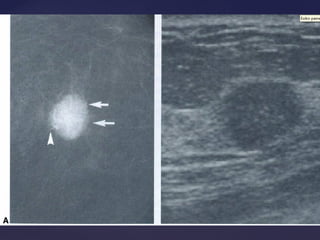

Descrição dos achadosDescrição dos achados

Distorção focal de arquitetura

linear/segmentar, distorção focal de arquitetura

Descrição dos achadosDescriçãodos achados Distorção focal de arquitetura